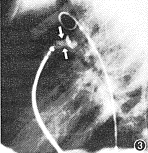

图2 封堵前主动脉弓降部造影示动脉导管未闭(PDA)呈漏斗状,最窄处直径约3 mm(↑)

图3 Amplatzer封堵器放置后呈“蜂腰”状(↑↓)